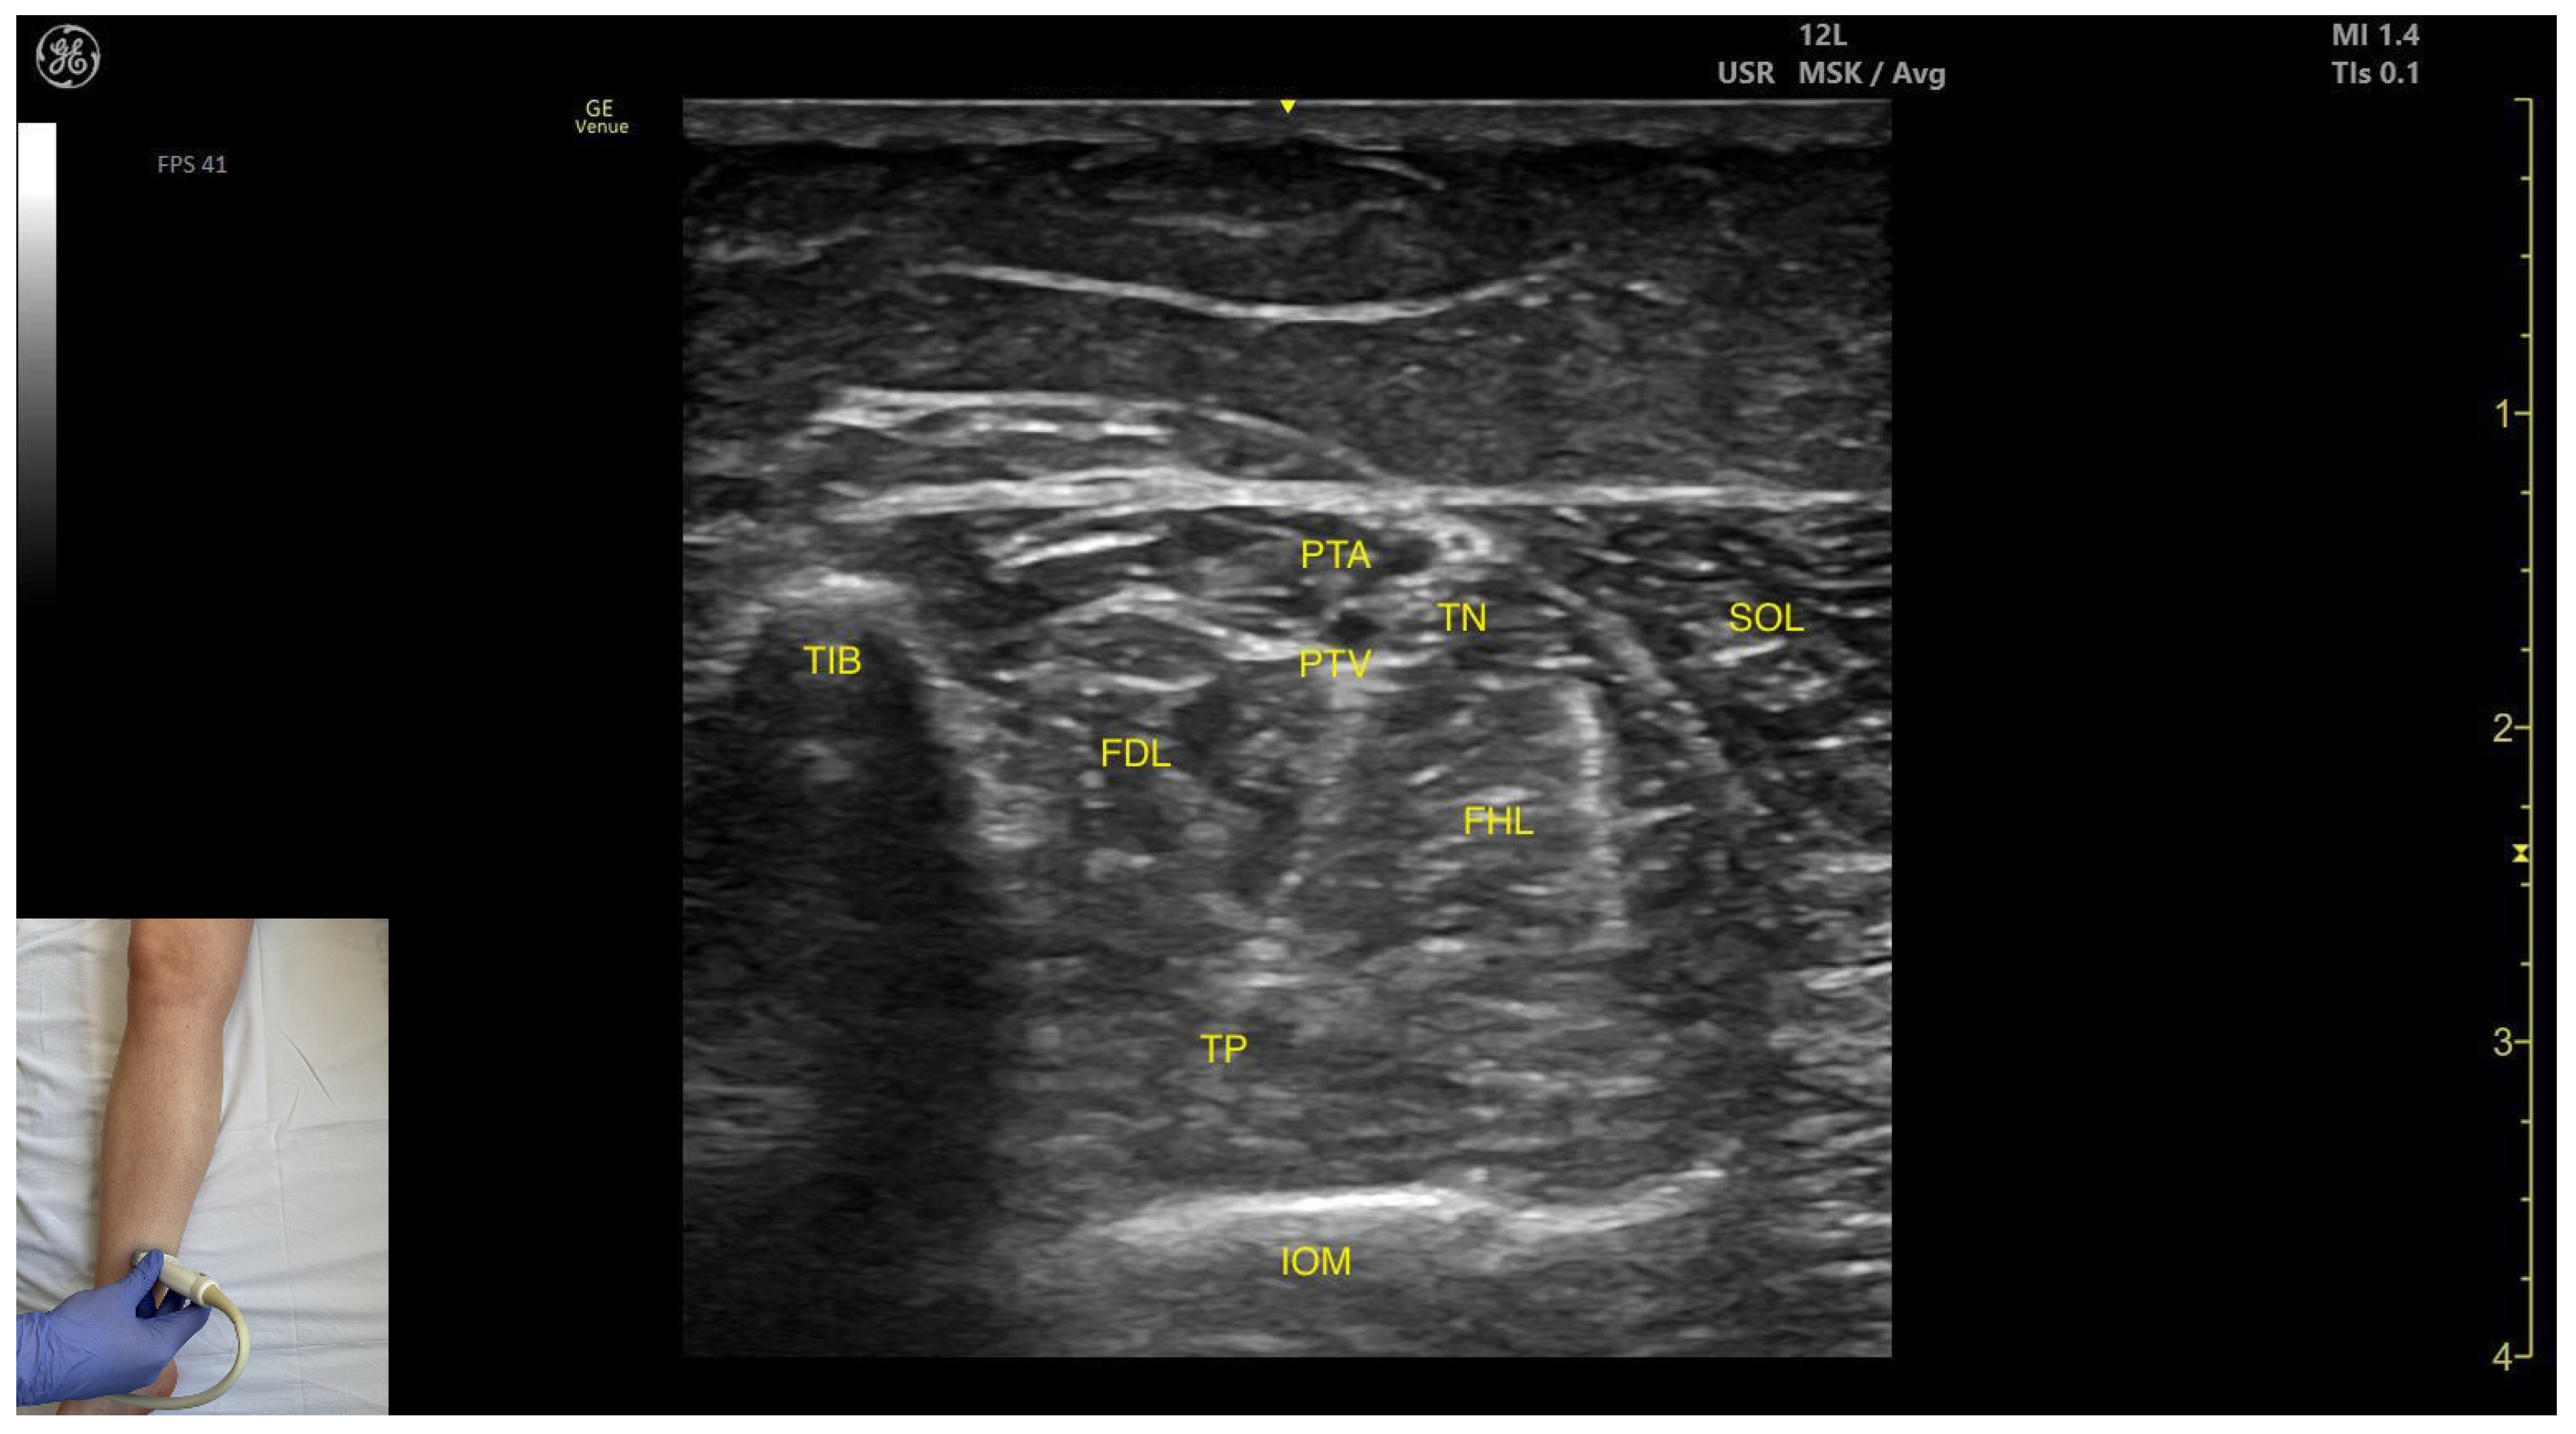

3.3.3. Medial Window

Ultrasound Identification

Key Ultrasound Landmarks

- Muscle position: The tibialis posterior is the deepest muscle in the posterior compartment of the leg. It is bordered superficially and medially by the flexor digitorum longus and superficially and laterally by the flexor hallucis longus. The interosseous membrane lies deep to the TP.

- Neurovascular bundle: Within the intermuscular fascial plane between the flexor digitorum longus, flexor hallucis longus, and soleus, the tibial nerve, posterior tibial artery, and posterior tibial vein are situated.

- External fascia: The TP does not have a well-defined fascia that separates it from flexor digitorum longus and flexor hallucis longus, during BoNT-A injection.

- Dynamic evaluation: Muscle contraction becomes evident during ankle inversion and plantar flexion at the ankle joint.

3.5. Flexor Digitorum Longus (FDL)

3.5.2. Ultrasound Identification

3.5.3. Key Ultrasound Landmarks

- Muscle position: It is located in the medial compartment of the posterior leg. Superficially, it is covered by the soleus; lateral to the FDL lies the flexor hallucis longus; deep and lateral to it lie the TP with the interosseous membrane located beneath it. At this level, the flexor digitorum longus and flexor hallucis longus are paradoxically reversed in position relative to their usual anatomical course.

- Neurovascular bundle: Within the intermuscular fascia between the flexor digitorum longus, flexor hallucis longus, and soleus are the tibial nerve, posterior tibial artery, and posterior tibial veins.

- External fascia: The FDL has a well-defined fascia that separates it from the soleus, which is relevant during BoNT-A injection. It does not have a pronounced fascia that separates it from the flexor hallucis longus and tibialis posterior.

- Dynamic evaluation: During dynamic evaluation, scanning proximally toward the knee joint, the flexor digitorum longus decreases in thickness and disappears from view, while the soleus increases in size and the medial head of the gastrocnemius appears superficial to the soleus (Video S2). Muscle contraction is visible during flexion of toes II–V (at metatarsophalangeal, proximal and distal interphalangeal joints) and ankle plantar flexion.

| FIB | Fibula |

| TIB | Tibia |

| TP | Tibialis posterior |

| FDL | Flexor digitorum longus |

| FHL | Flexor hallucis longus |

| PTA | Posterior tibial artery |

| PTV | Posterior tibial vein |

| TN | Tibial nerve |

| IOM | Interosseous membrane |

| Tibialis Posterior (medial window) | Distal third of the leg, in the medial portion | Flexor digitorum longus (superficial and medial), flexor hallucis longus (superficial and lateral); tibial nerve, posterior tibial artery, and posterior tibial vein (superficial); interosseous membrane (deep) | Transverse scan on the distal third of the leg | Avoid neurovascular injury |

| Flexor Digitorum Longus | Distal third of the posterior leg in the medial portion | Soleus (superficial); flexor hallucis longus, tibial nerve, posterior tibial artery, and posterior tibial veins (lateral); tibialis posterior, interosseous membrane (deep and lateral); | Transverse scan distal third of the posterior leg | Avoid neurovascular injury |